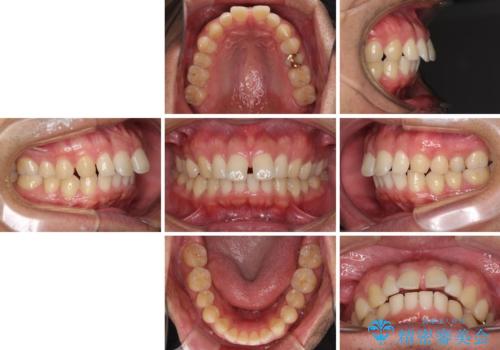

- 上顎前歯の突出感とすきっ歯を気にして来院された患者様です。

奥歯の咬み合わせを見ると、下顎に対して上顎が前方に位置していたため、補助装置により上顎歯列全体を後方に移動させ、その後インビザラインにて歯列全体を整えることとしました。

インビザライン開始前に奥歯の咬み合わせを変える補助装置は幾つかあります。

咬み合わせの強さや下顎の歯列の状態などによって、最適な補助装置を選択しています。

インビザライン単独で咬み合わせを改善することもできますが、治しきれない可能性が高いため、事前に補助装置で治しておくことは、治療の仕上がりの点で非常に重要となります。